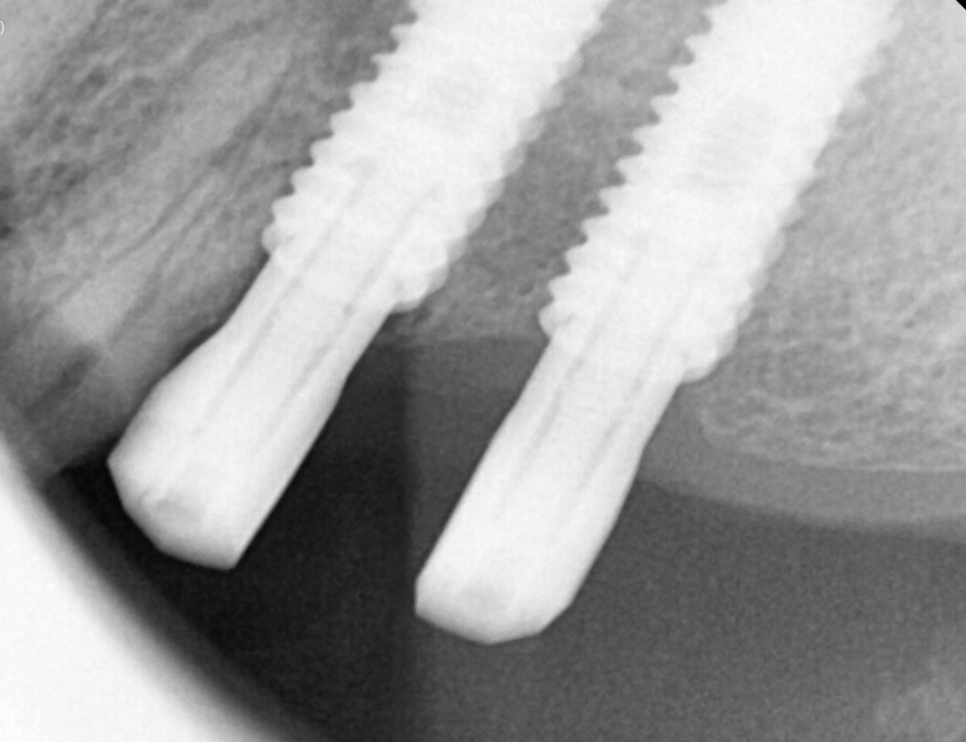

우리의 생각으로는 일자로 임플란트가 박힌 것 같지만

각도에 맞춰서

윗니가 아랫니를 덮을 수 있게 심어주어야한답니다.

여기에 보철을 연결한 모습을 확인하면,,